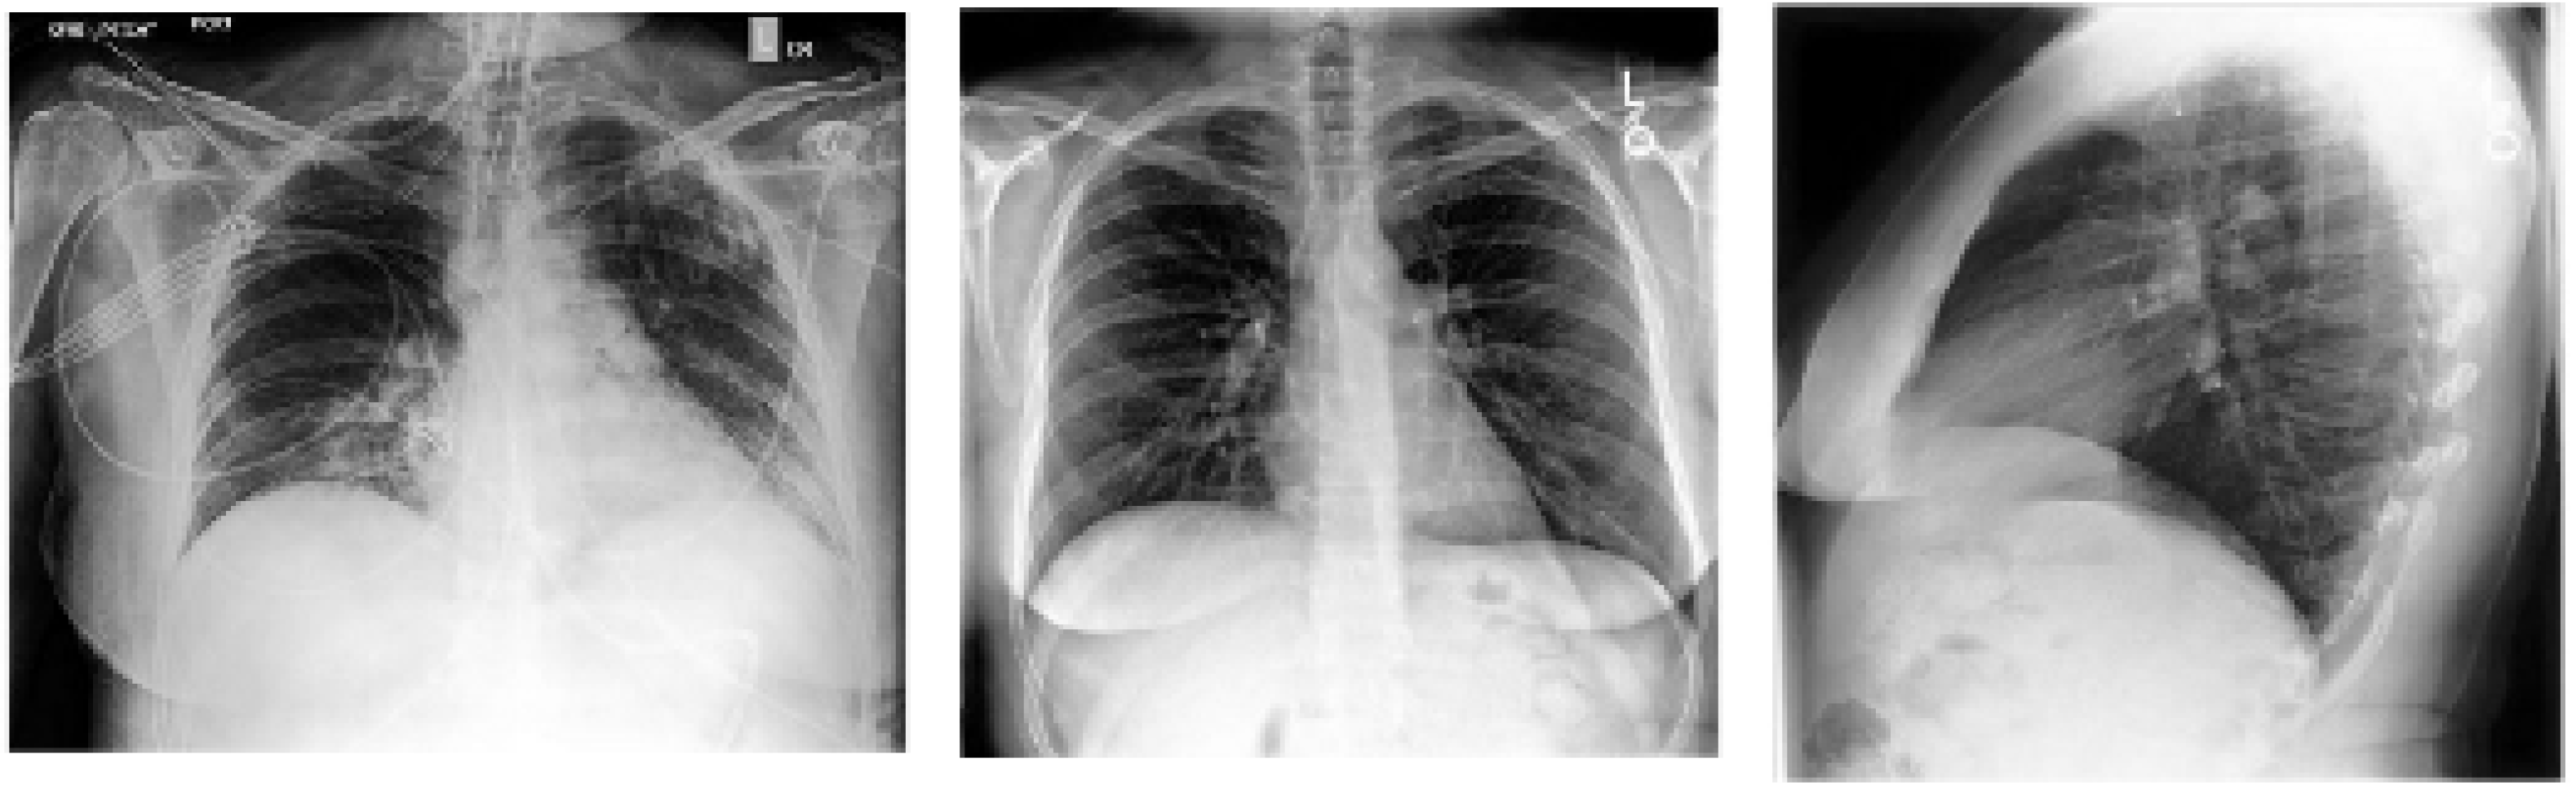

X-ray imaging is one of the most common techniques used in clinical and other healthcare settings for the diagnosis of a wide range of diseases. The advantages of X-ray imaging over other imaging techniques include low radiation, availability (i.e., due to high demand), low cost, moderate sensitivity, and low radiation dose [90]. The classification of chest X-ray images by radiologists include posteroanterior, anteroposterior, and lateral views, as shown in Figure 5. These classifications are based on the position and orientation of patient parallel to the X-ray source and detector panel. Side view or lateral view differs from both anteroposterior and posteroanterior (which are known as frontal views). The side view is obtained as a result of the combination of posteroanterior view and projection of the x-ray from one side of the patient to the other or right to left. The frontal views are based on the positioning of the X-ray source to the front or rear of the patient. Posteroanterior X-ray imaging is generated in erect standing position of the patients, while anteroposterior X-ray image is obtained from patients in the supine position [90,91].

Figure 5.

Left: Anterior–posterior (AP) view chest X-ray. Middle. Posterior–anterior (PA) view frontal chest X-ray. Right: lateral chest X-ray.